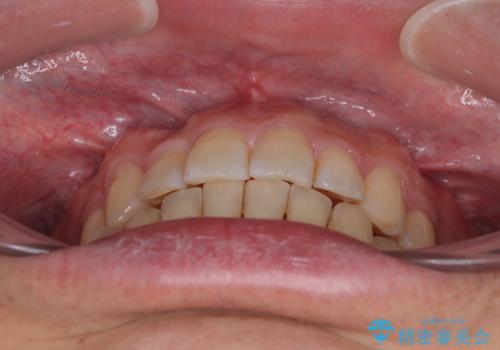

- 上下前歯のデコボコを気にして来院された患者様です。

上顎前歯の舌側転位が顕著であったため、治療期間が長くなると思われましたが、僅か1年で無事に終えることができました。